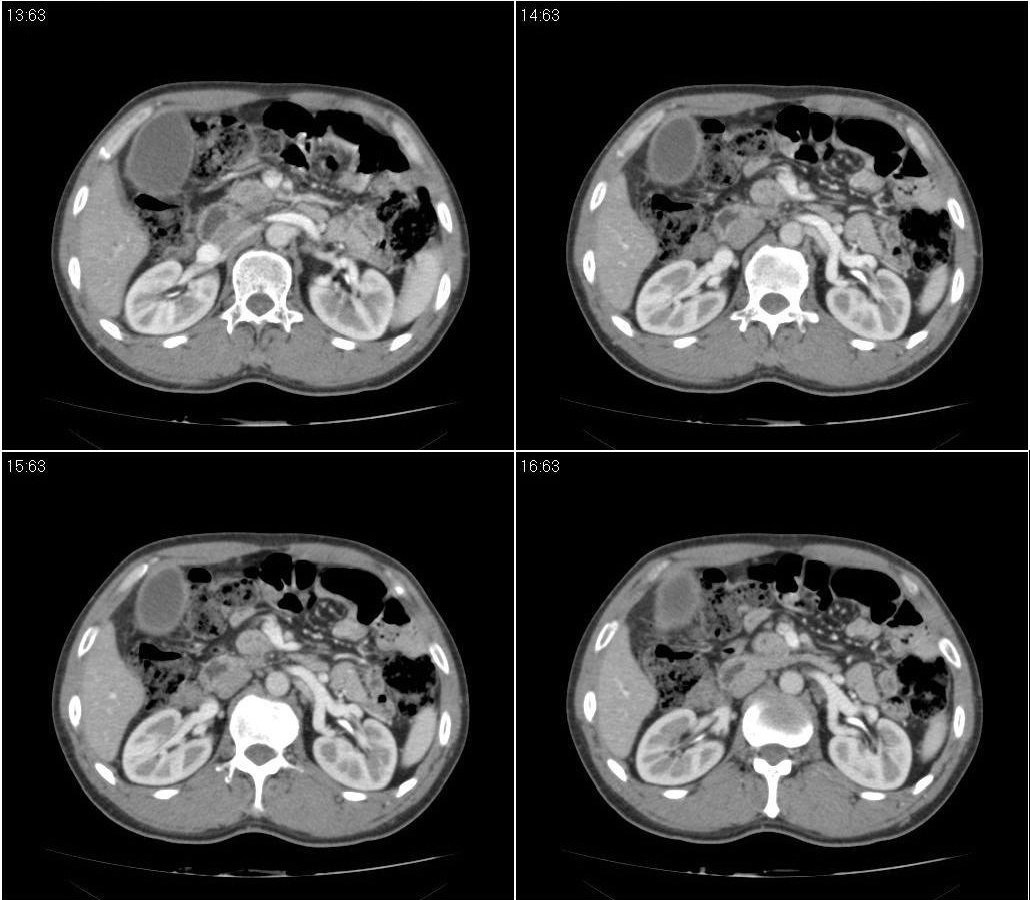

标题: CT21384:男性,50岁。发现无痛性黄疸十余天,B朝提示肝胆管 [打印本页]

标题: CT21384:男性,50岁。发现无痛性黄疸十余天,B朝提示肝胆管

1.考虑:壶腹占位病变(癌?)。

2.胆系低位梗阻:肝内外胆管扩张,胆囊增大,胰管扩张。

胰头癌伴低位胆道梗阻。

胆系低位梗阻(肝内外胆管扩张,胆囊增大,胰管扩张);考虑胰头癌或壶腹癌所致。

胆总管突然中断,壁增厚且强化,考虑胆总管癌可能性大伴胆系梗阻,胆囊炎

胰头强化欠均匀,胆胰管扩张。考虑胰头癌可能性大。

胆系低位梗阻(肝内外胆管扩张,胆囊增大,胰管扩张,钩突似有占位);考虑胰头癌